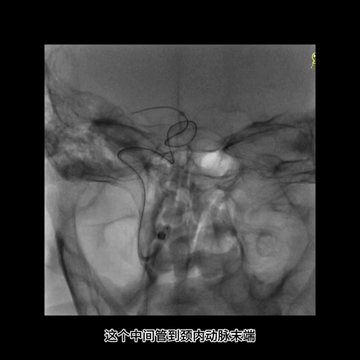

中间管内衬.018"导丝(Command 18),并尽力推高长鞘,在增强支撑下把中间管头端推送至颈内动脉末端,以增加对微导管微导丝的支撑性。

微导丝配合下,微导管首先通过闭塞血栓位置进入M2下干,导丝跟进把微导管送至M2下干中远段,造影证实位于真腔后,送入取栓支架Trevo 4*20mm,释放支架后恢复前向血流,支架完全覆盖病变,血栓负荷较大。